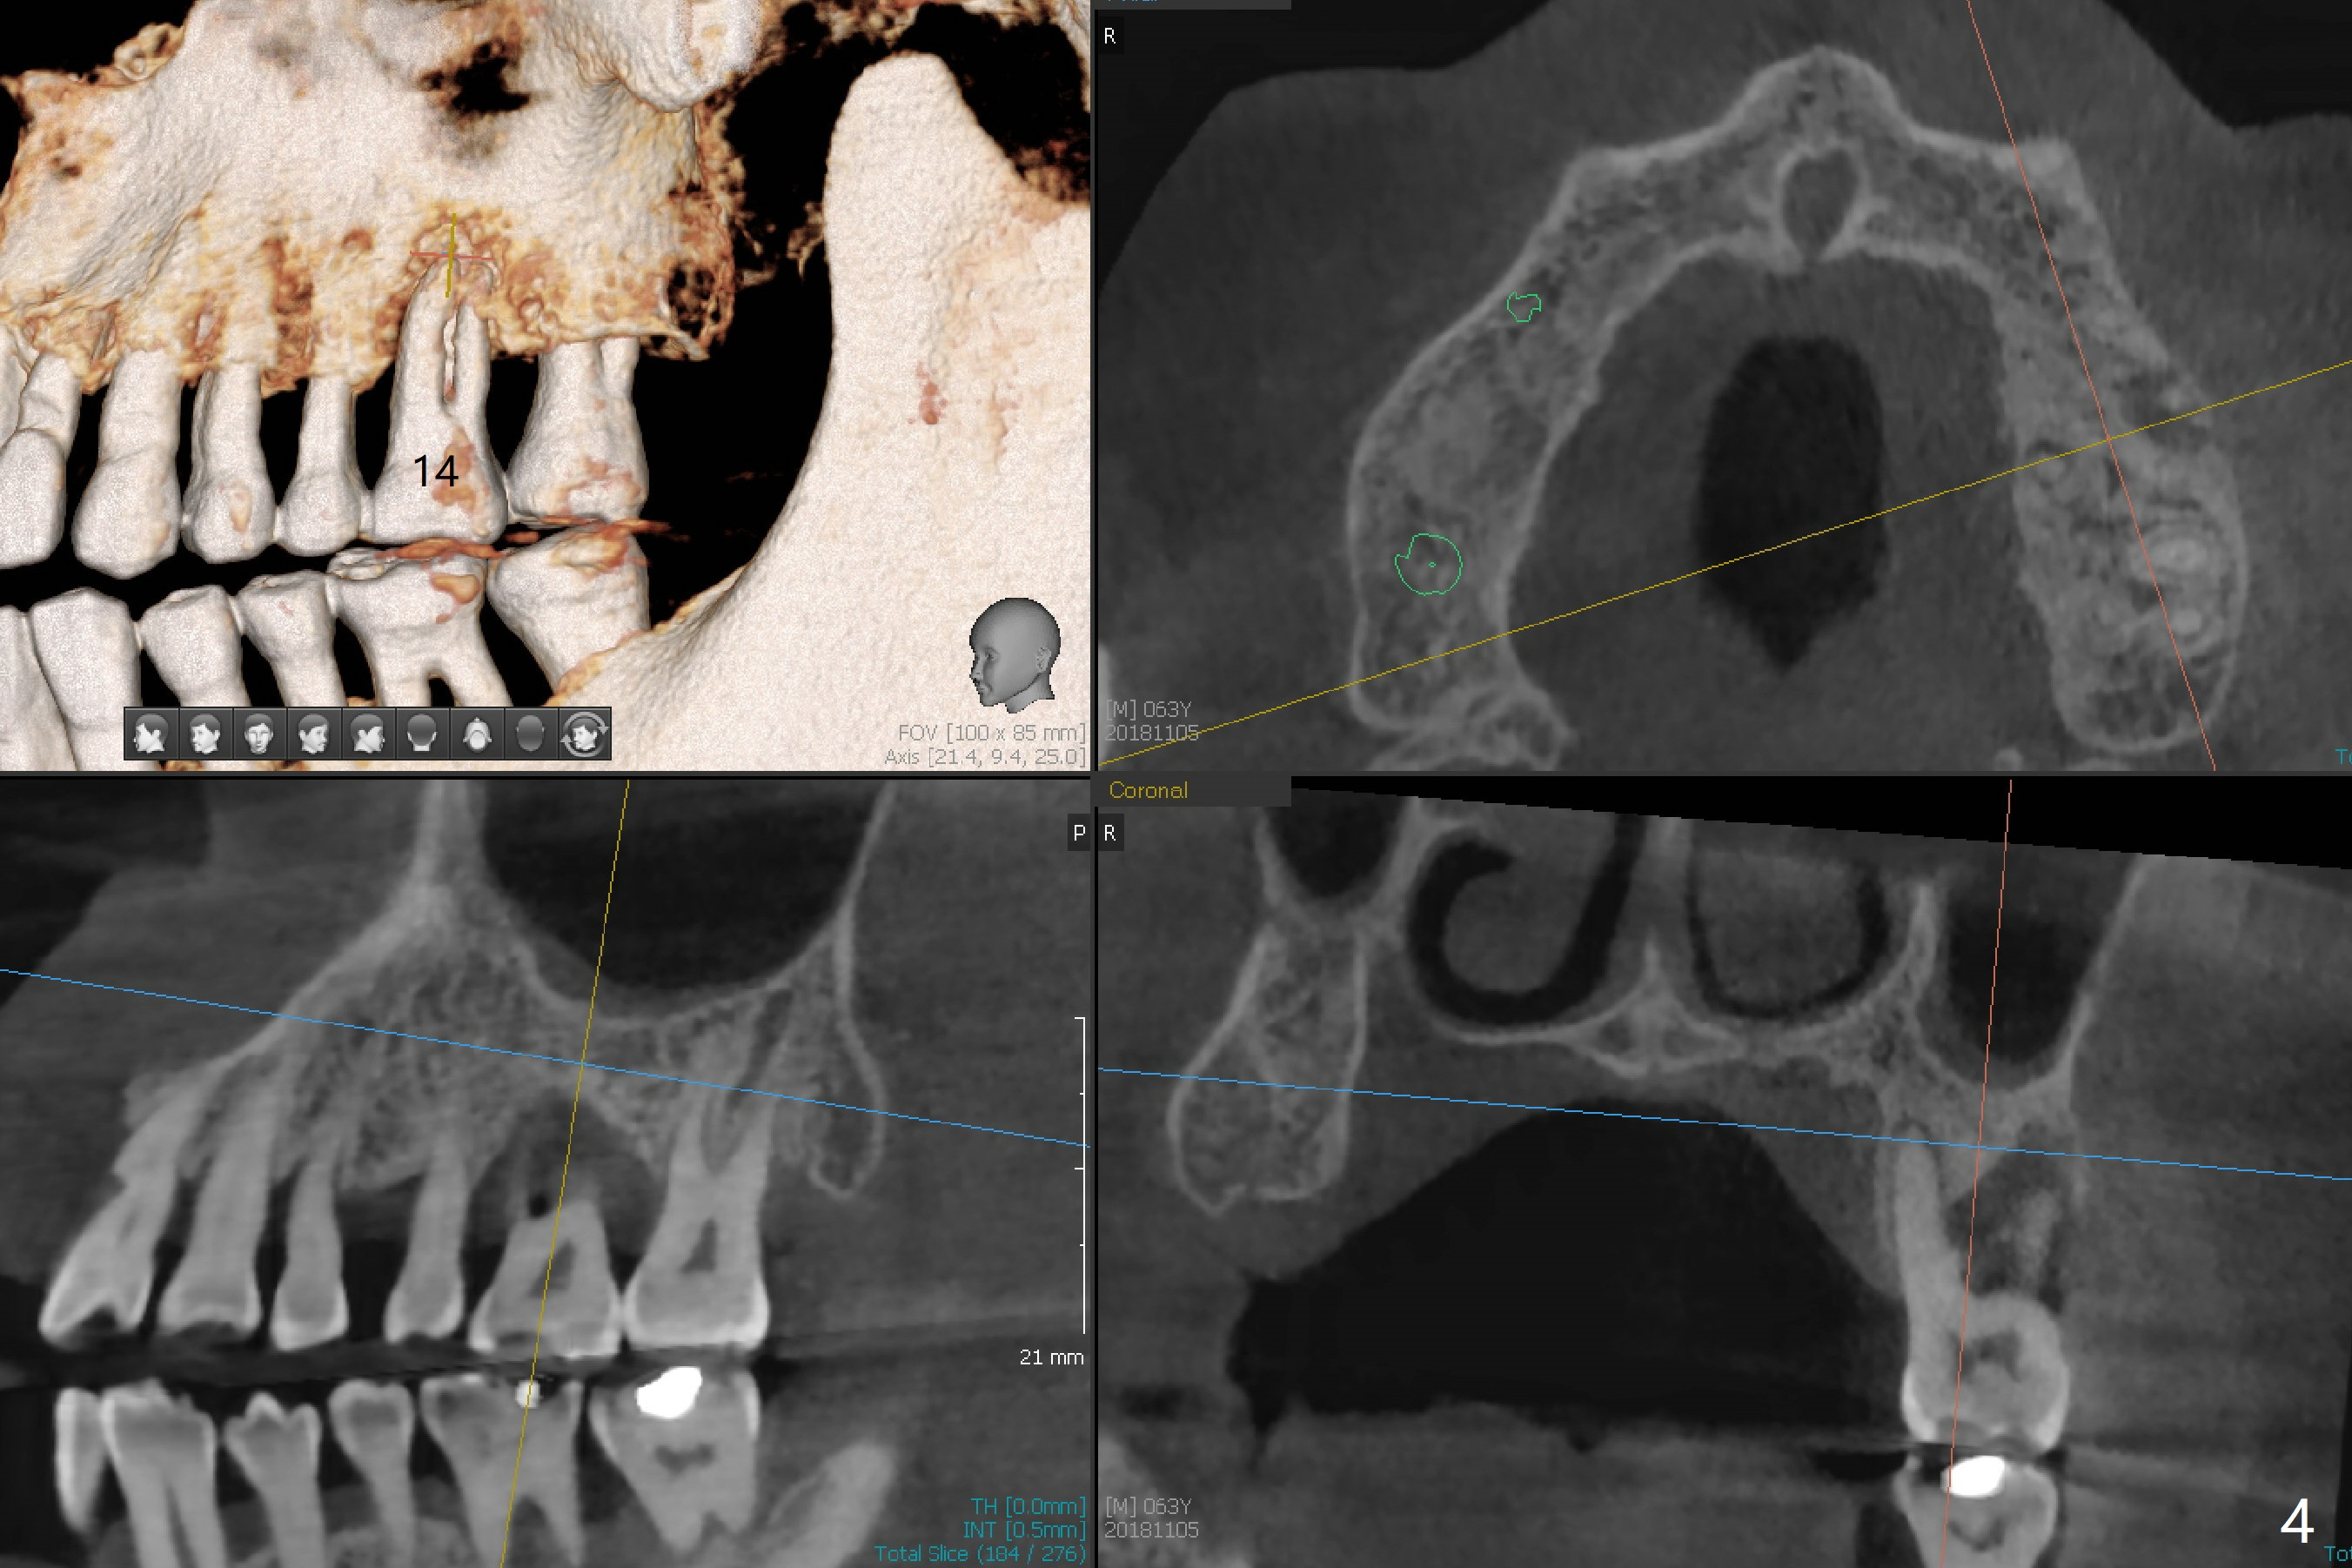

A 63-year-old man lives out of state and returns to office for scaling with chief complaint of occasional upper left pain (#14, Fig.1). After discussion, he agrees to have implant restoration in the upper right quadrant (#2-4). It appears that a 3-unit FPD is appropriate (Fig.2,3). When the teeth #14 and 19 fail, immediate implants will be placed (Fig.4-6).